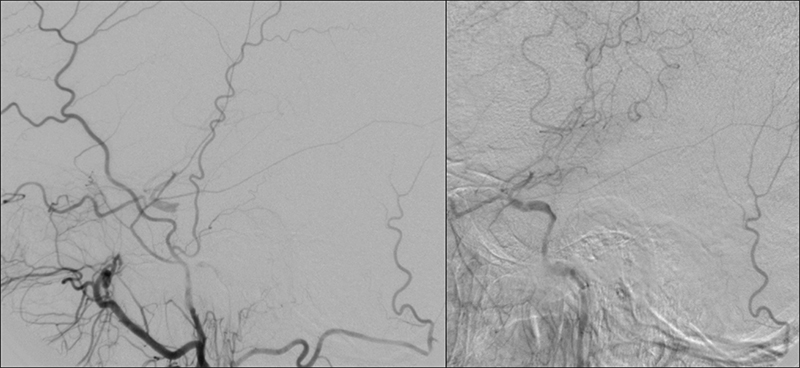

Εικόνα 3 και 4: Προσθιοπίσθια και πλάγια ενδοκράνια λήψη εγχύσεως στην αριστερή κοινή καρωτίδα. Υποτυπώδης ροή μόνο προς την αριστερή μέση εγκεφαλική (έμμεσο στοιχείο κινητοποιήσεως της παράπλευρης κυκλοφορίας από την αντίστοιχη πλευρά).

Εικόνα 6: Προσθιοπίσθια ενδοκράνια λήψη εγχύσεως στην δεξιά κοινή καρωτίδα. Κίνητοποίηση της παράπλευρης κυκλοφορίας διά μέσου της προσθίας αναστομωτικής αρτηρίας με άρδρευση πλήρως της αριστερής πρόσθιας εγκεφαλικής και συμμετοχή στην άρδρευση της αριστερής μέσης εγκεφαλικής αρτηρίας.